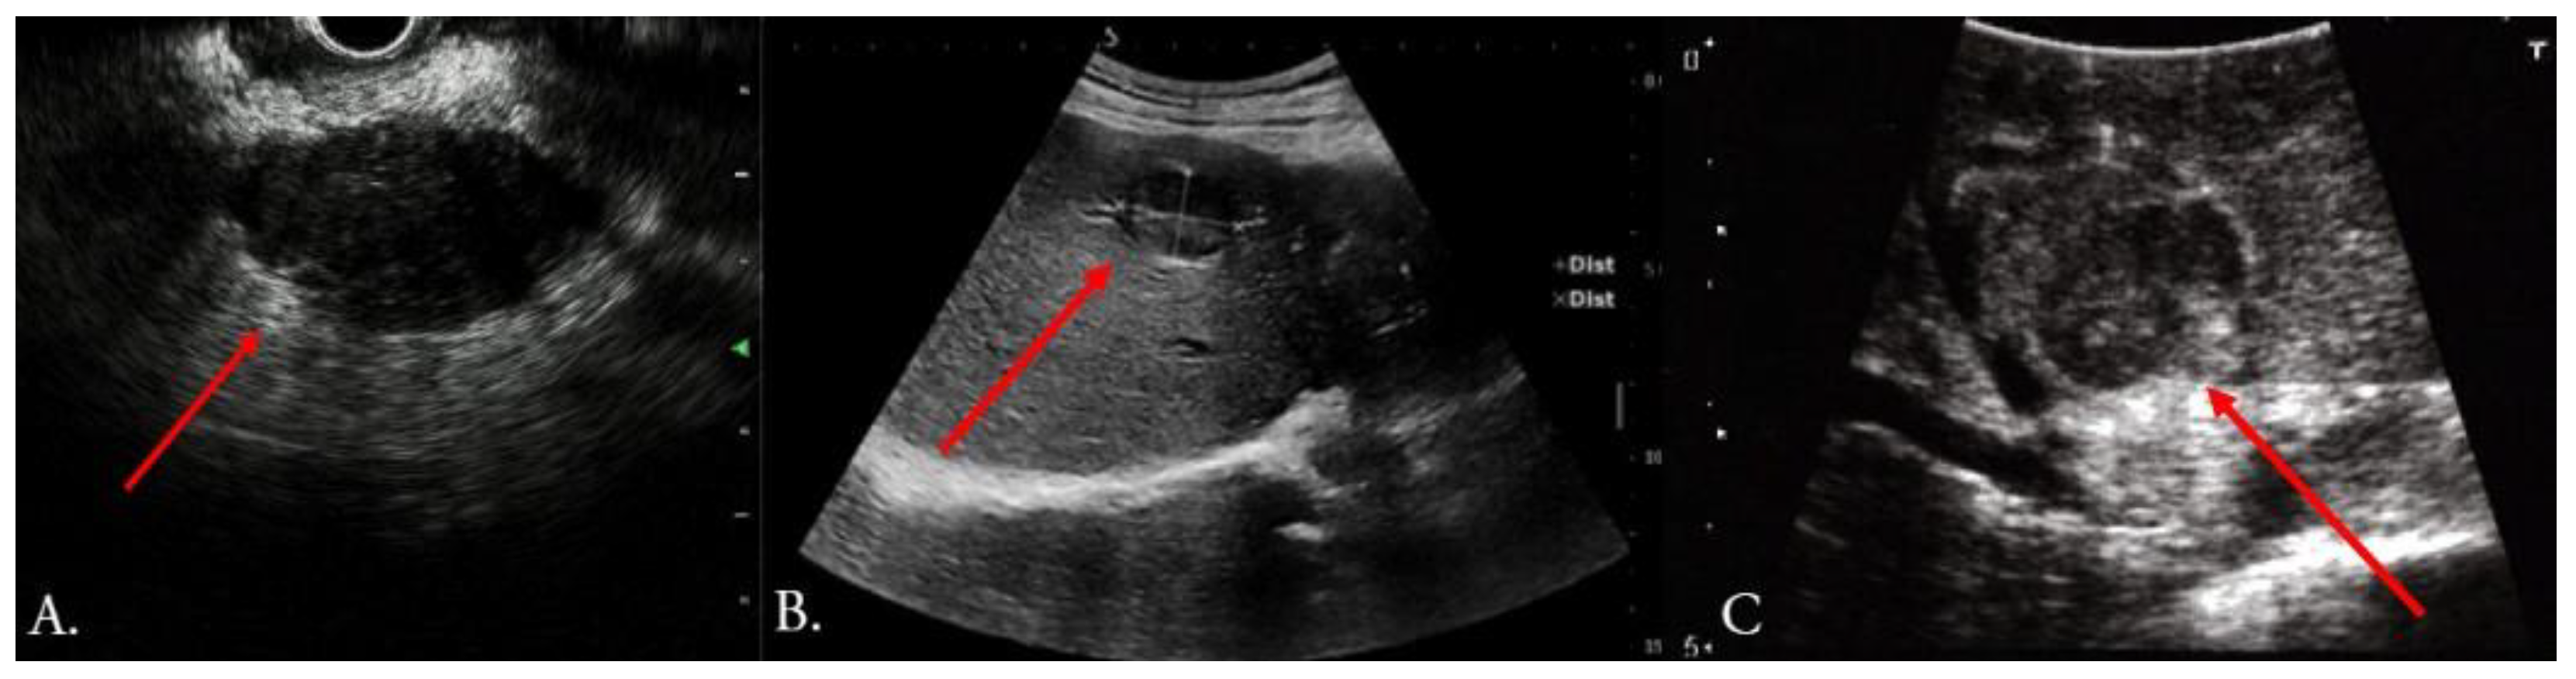

Figure 2.

Commonly used ultrasound methods (red arrow indicates mass): (A) endoscopic ultrasound of pancreatic lesion, (B) preoperative transabdominal ultrasound of HCC liver lesion, (C) intraoperative ultrasound of HCC liver lesion close to the vasculature (identical lesion to image (B)). Original figure.